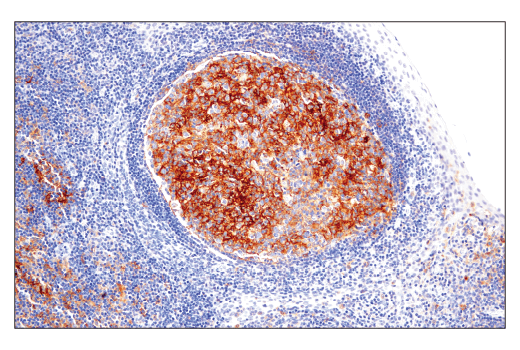

W, IHC-Bond, IHC-P, IF-IC

W: Western Blotting IHC-Bond: IHC Leica Bond IHC-P: Immunohistochemistry (Paraffin) IF-IC: Immunofluorescence (Immunocytochemistry)